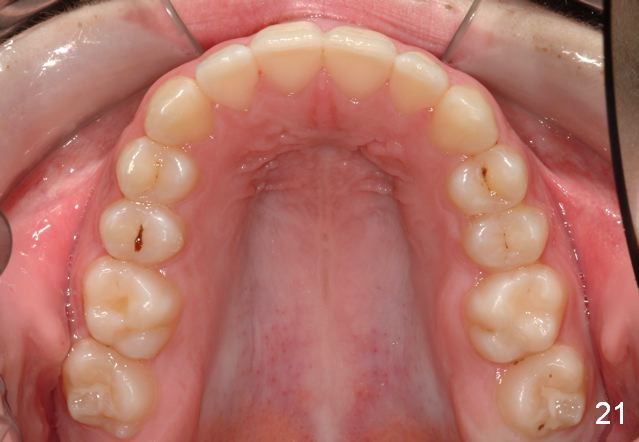

Final Results of Unilateral Class II Malocclusion

After using Rapid Molar Distalizer.  Total treatment lasts 50 months.